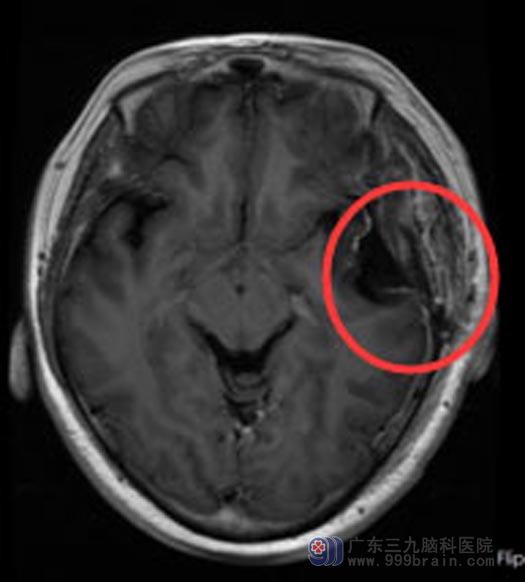

进一步检查发现肿瘤较之前有所增大,考虑脑膜瘤,家属同意手术治疗。鲁明主任主刀在全麻下行“左侧颞部脑膜瘤切除术+硬脑膜修补术+颅骨成形术”,显微镜下顺利将肿瘤全切除。术后病理:左颞过渡型脑膜瘤,WHO1级。

手术后